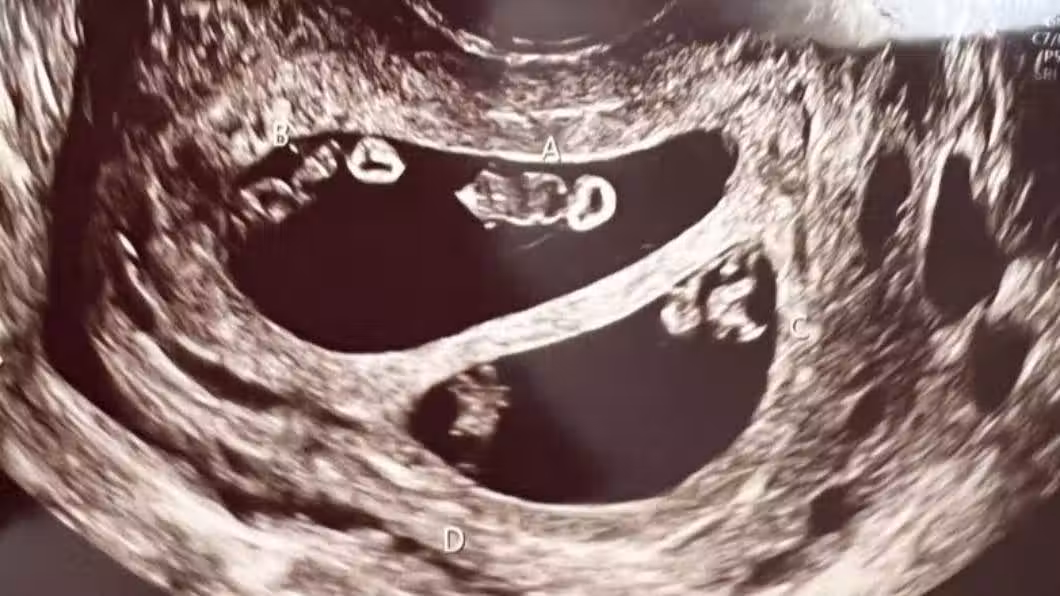

以為是懷雙胞胎!醫生幫她照超音波「疑惑緊盯螢幕」 走出房間驚呼「千萬分之1的奇蹟」全場嚇傻

醫生在照超音波時發現驚人景象,艾希莉本來以為自己是懷著一對雙胞胎寶寶,沒想到醫生疑惑的看著螢幕好久,又走出房間請同事一起來觀察,最後才確定她竟然懷上了2對同卵雙胞胎,分別為2男2女,而醫師也解釋這狀況在醫學上發生機率僅7千萬分之一,根本就像是中了一張大樂透般不可思議!